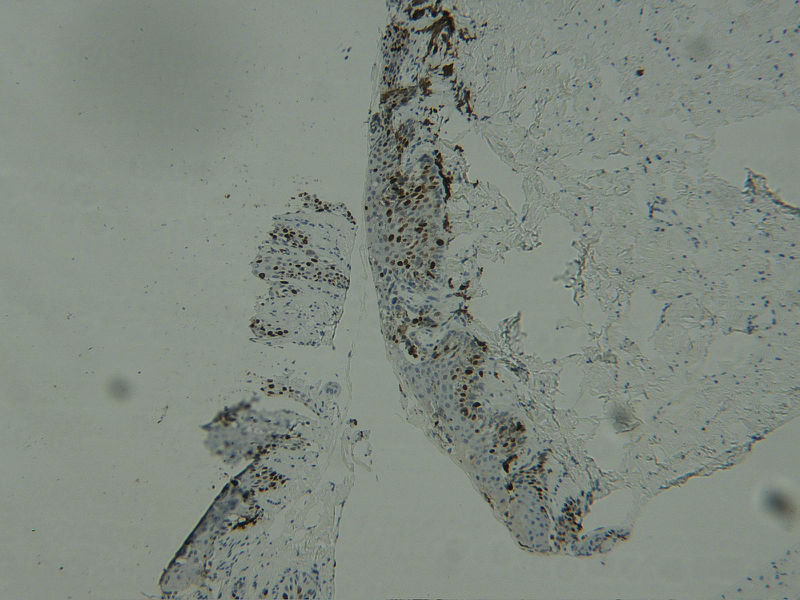

图1HMB45

图2HMB45

图3HMB45

图4Ki-67

女 68岁 右手拇指甲变黑及扩散2年,无自觉症状,有风湿性关节炎病史数年。

无论临床和病理上均符合甲下原位黑素瘤的诊断,临床上线状黑斑的宽度大于3mm,且甲皱襞有累及,年龄偏大;

病理上:甲上皮基底层见异型黑素细胞(非常明显的异型)增生,部分向表皮上部扩散,诊断原位黑素瘤。免疫组化不需要做的,因为就该病人来说,免疫组化不能帮助区别是良性还是恶性的,HE的改变已很典型了。

表皮见黑素细胞增多、成巢,轻度异型,可见向Paget样扩散,临床上黑斑累及甲皱襞,甲下黑素瘤还是要排除。不知有无做免疫组化。